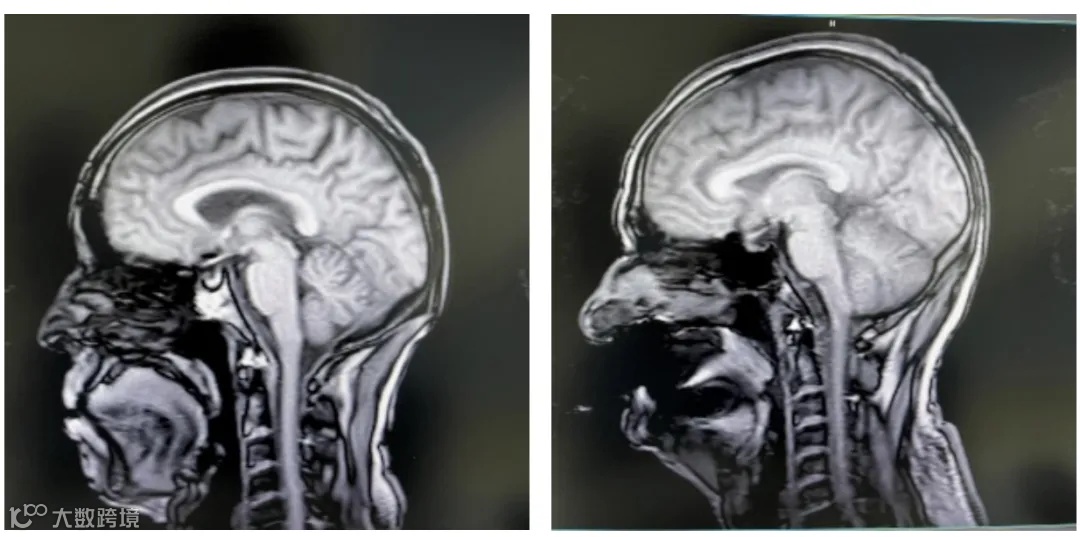

左:头部失状扫描图;右:假牙干扰后的伪影

③ 在进行盆腔检查中,金属节育器可能会引起图像失真。